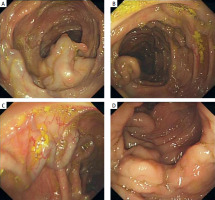

A 45-year-old male patient was referred to our hospital with a 1-day history of melena, dizziness, palpitations, weakness, and transient loss of consciousness. On examination, he appeared pale. Laboratory tests were all within the normal range except for iron deficiency anemia (Table I). Chest and abdominal computed tomography (CT) were unremarkable. Gastroscopy revealed no bleeding site. An ultrasound scan of the abdomen showed normal appearance of the liver, spleen, and pancreas. No signs of thrombosis of the portal axis were detected in Doppler examination. Colonoscopy revealed exaggerated vasculature of the colon (varices) (Figure 1). Mesenteric CTA indicated tortuous and increased varicose veins in the transverse colon, ascending colon and small intestine (Figure 2). The case was discussed, and a decision was made to proceed with internal medicine conservative treatment with fasting, nutritional support, and fluid therapy. The patient made an uneventful recovery and was discharged. The patient had hemorrhage of the digestive tract again 1 year later. The evidence again demonstrated total colonic varices, and the patient was advised surgery but declined the procedure.

The diagnosis and etiology of idiopathic colonic varices are difficult to determine, and require laboratory and imaging tests to rule out secondary causes. Relevant tests to be completed include: blood routine, liver function, hepatitis serology, liver ultrasound, portal vein ultrasound, portal venography, and liver elastography. CT angiography or mesenteric angiography is the most accurate diagnostic tool [7]. Angiography shows dilated vessels and prolongation of the venous phase. Colonoscopy is a diagnostic option. During the endoscopy, colonic varices are identified by dilated, tortuous vascular tracts with a bluish tinge on the mucosal surface. Our patient was diagnosed appropriately with colonic varices through CT angiography and colonoscopy.